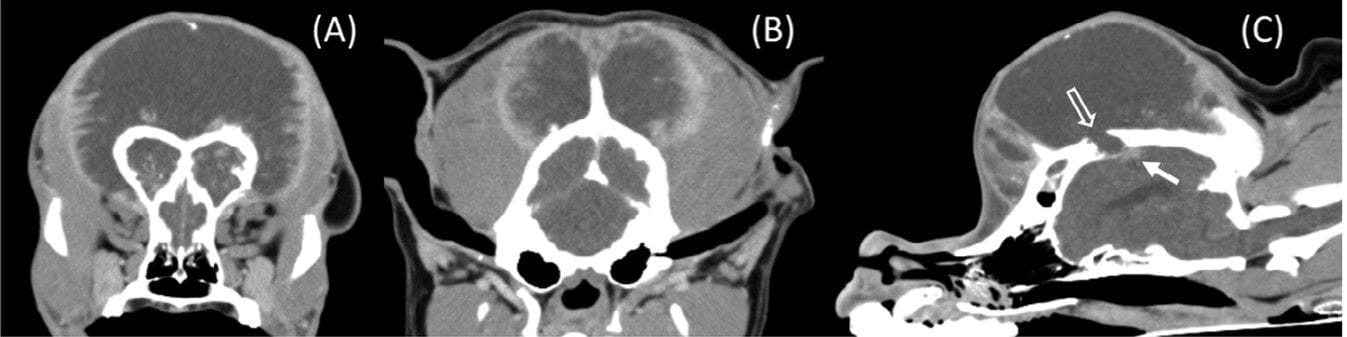

(A–C) Transverse postcontrast CT images in a soft tissue window at the level of the frontal sinuses (A) and more caudally, at the levelof the tympanic bullae (B) as well as a sagittal image just right of midline (C). Caudally, the mass has a more bilobed appearance, with the enhancingrim extending from the abaxial dorsal calvarium in addition to the external occipital crest. In image (C), just caudal to the region of lysis of the dorsalcalvarium (open arrow) is an ovoid region of contrast-enhancement within the underlying brain parenchyma (white arrow)

CT imaging revealed a large, symmetrical, hypoattenuating cranial mass with a strong contrast-enhancing capsule but minimal mineralization. Adjacent bone lysis and a small enhancing intracranial lesion were observed, suggesting aggressive behavior. Histopathology confirmed a Grade III MLO composed of pleomorphic mesenchymal cells surrounding cartilage and bone lobules, with extensive necrosis and local invasion into adjacent tissues. Postmortem examination also identified a pulmonary tumor embolus. The tumor was encapsulated and likely arose from the periosteum.